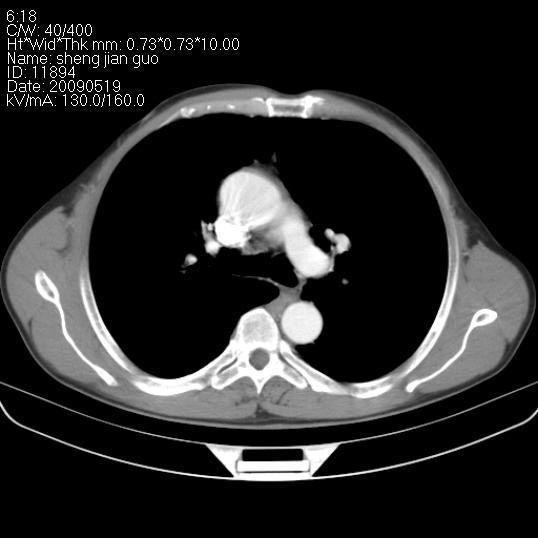

以下是引用zjzjr在2009-5-19 17:25:00的发言:[br]支持楼主考虑,另左肺下叶阻塞性炎症。

以下是引用zhao_bin2008在2009-5-19 17:48:00的发言:[br]支持左肺下叶周围型肺癌并阻塞性肺炎。

以下是引用zsl6918在2009-5-20 7:10:00的发言:[br]左侧中心型肺癌!